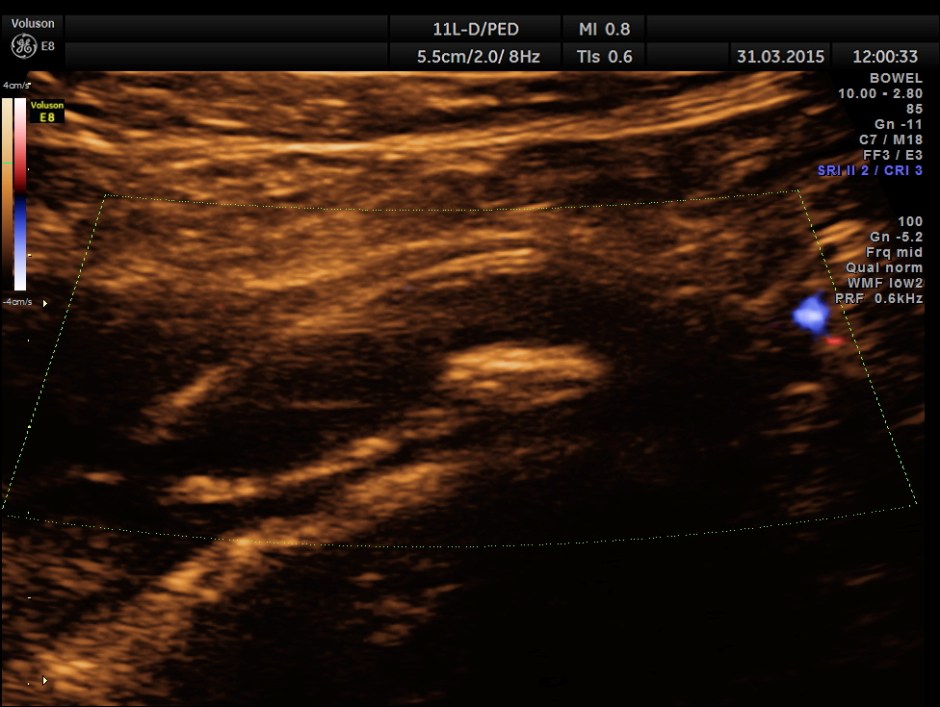

Colour Doppler shows vascularity of the wall . It was non pulsatile and non collapsible.

This patient had some misleading signs and symptoms . It is always better to establish the ” connection” between the dilated ureter and the kidney. Usually appendix is picked up better with high resolution transducers. But in this patient , it was well picked up with a routine abdominal transducer. The colour doppler was useful in this patient also.